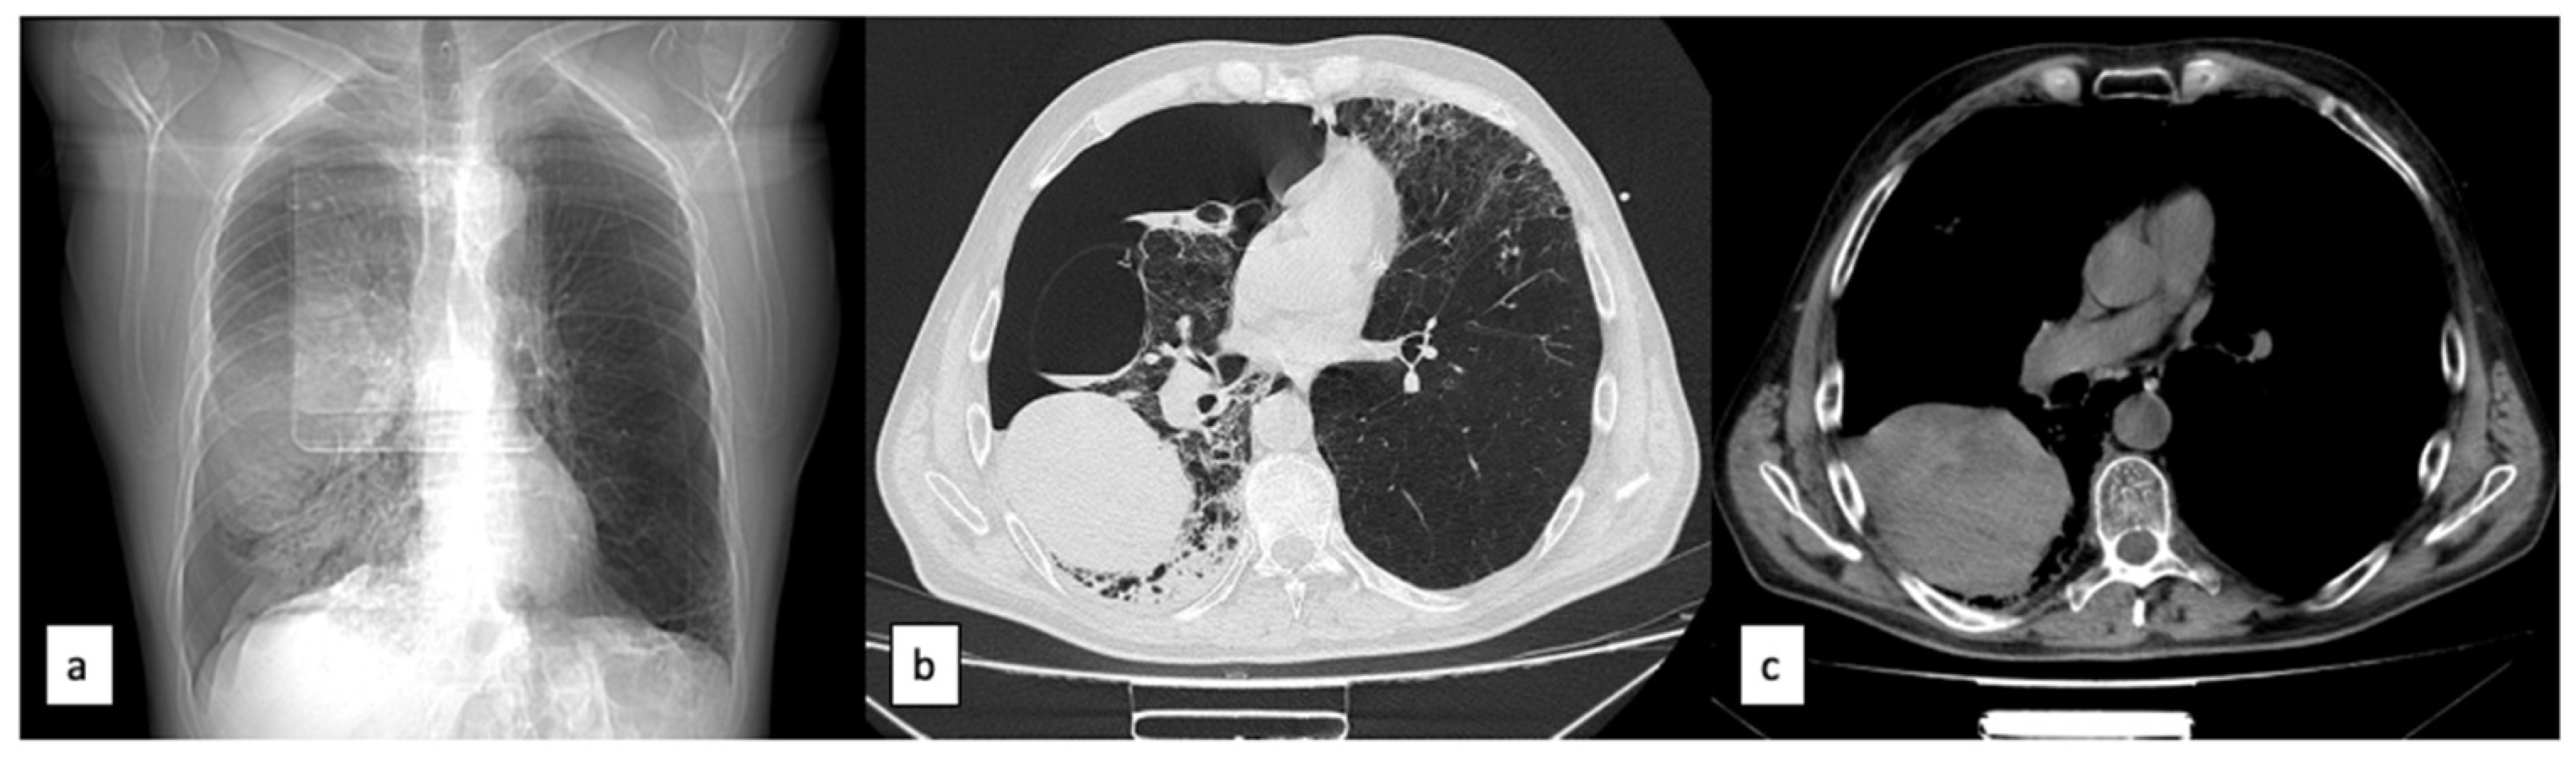

2. Case Report

3.2. Imaging Diagnosis

3.3. Clinical Course and Treatment